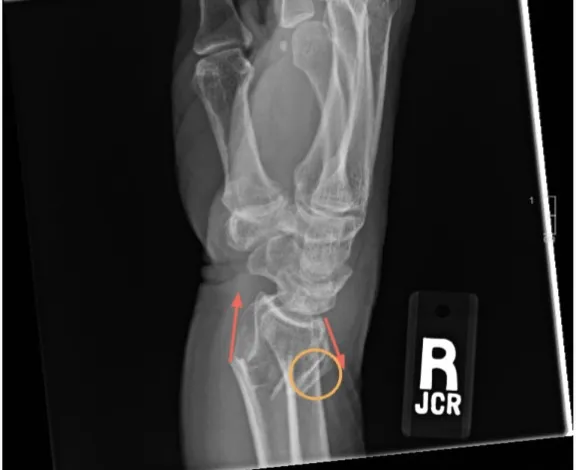

🦴 Radiology - Reading the Cracks

- 2 Views: At least two orthogonal views (e.g., AP & Lateral at $90^\circ$).

- 2 Joints: Image the joint above and below the suspected fracture.

- Describing Fractures (The 4 A's):

- Alignment: Relationship of the longitudinal axes of fracture fragments.

- Angulation: Deviation of the distal fragment from the normal axis.

- Apposition: Percentage of fracture surface contact.

- Displacement: Shift of the distal fragment relative to the proximal.

⭐ A negative X-ray does not rule out a fracture. High-risk injuries (e.g., scaphoid, femoral neck) with negative initial films warrant further imaging (CT/MRI) or repeat X-rays in 7-14 days.

- Special Views: Often required for anatomically complex areas (e.g., scaphoid view, ankle mortise view).